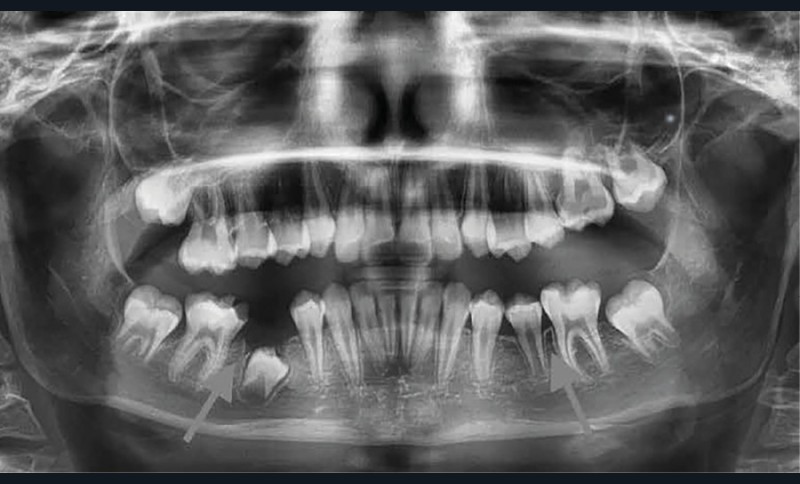

Lisa est une jeune patiente de 10 ans, atteinte d’une MIH sévère sur les premières molaires mandibulaires 36 et 46 (fig. 1 et 2). Elle présente une sensibilité exacerbée au froid en regard des zones molaires entraînant un brossage approximatif.

Il a été décidé de réaliser des coiffes préformées métalliques sur les premières molaires permanentes pour supprimer les sensibilités et restaurer les fonctions mécaniques. Au regard de l’immaturité des tissus parodontaux et de l’anxiété de Lisa, la réalisation d’onlays n’a pas été envisagée.

Afin d’optimiser les séances de soins, l’anesthésie intra-osseuse par injection électronique a été réalisée avec le Quicksleeper 5® dans les deux secteurs (fig. 3 et 4) afin de permettre la réalisation des coiffes préformées métalliques sur 36 et 46 dans la même séance (fig. 5 à 7). Il aurait été difficilement envisageable de réaliser les coiffes dans la même séance en utilisant une anesthésie tronculaire dans chaque secteur.